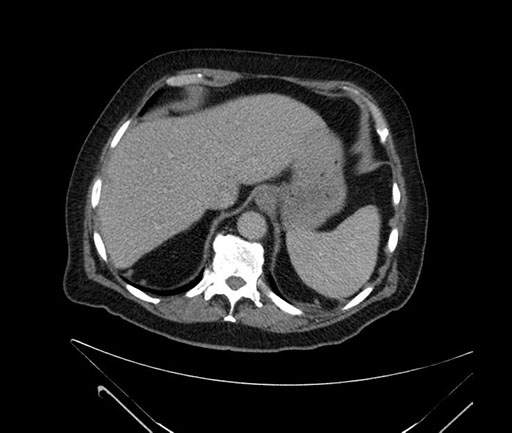

Whipple (pancreaticoduodenectomy) [case 7]

Imaging Analysis

Look through the patient's CT scan to identify any areas of concern for the necessary procedure.

Axial - stented